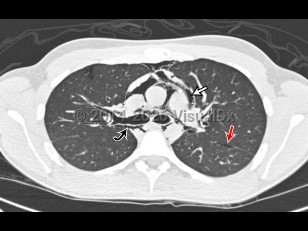

Pneumomediastinum is the presence of air in the mediastinum. It is caused by injury, most often esophageal or intestinal perforation. It can rarely occur spontaneously in children with acute asthma attacks (severe cough) and is also seen as a result of aggressive bag-valve mask ventilation during resuscitation and intubation as well as a result of barotrauma in intubated patients.

Pneumomediastinum in Infant/Neonate